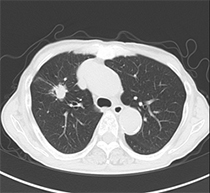

肺がん

肺がんの中で腺がんの多くは、胸部CT検査で発見できます。

しかし、喫煙者に多い扁平上皮がんは、太い気管支の内側に発生することが多く、胸部X線やCT検査などには映らない場合があります。

太い気管支に発生した扁平上皮がんは、喀痰の細胞診検査で見つけやすいので、肺ドック プレミアムコースでは、喀痰細胞診をセットにしました。